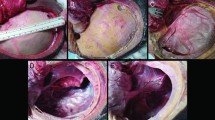

The idealized of brain geometry model, shown in Fig. 1, is developed based on spherical shape suggested by [8]. The brain model is developed by a half sphere with a hole of half spherical at the center, which indicating the lateral ventricles. Another sphere is constructed within the geometry of half spherical to indicate the infarct of ischaemic. Then, 3D brain model is layered by another half spherical with an opening to represent the skull geometry with DC surgery.

A simulation of an idealized 3D brain model was performed to evaluate the outcome of DC surgery using different size of skull opening in reducing the midline shift after 5 h of ischaemia–reperfusion. For a simple visualization, the simulation results displayed below based on part of brain that been sliced half through infarcts and skull opening, in which take part at the brain geometry centre.

Figure 2 shows the displacement of tissue of brain for infarct radius of 14 mm with different skull opening sizes. Midline shift that takes place in the middle of ventricle is also known as the brain herniation. In clinical study, brain herniation is used as indicator to predict the severity of brain tissue swelling in stroke [9, 10]. Based on Fig. 2, skull opening size of 30 mm experiences the least herniation compared to the skull opening of 10, 15 and 25 mm of skull opening size. This is because the skull opening causes the reduction of ventricle compression by allowing the brain tissue to swell towards the opening. Even though DC surgery has been proven to reduce the elevation of ICP [11] in brain as well as to reduce herniation, this surgery may also contribute some complications that still need to be considered.

Further, Fig. 3 shows that the skull opening size of 10 mm experience major stress in between the opening edges and brain tissue. This is because, small skull opening size increases the compression at the opening edges and also due to high brain tissue strain to bulge out from the skull. This may increase the risk of brain tissue damaged and infections [12].

Meanwhile, the largest skull opening size of 30 mm shows a much higher stress in between the edges of DC opening. Although the larger size of opening reduce the herniation, it may increase the risk of hydrocephalus development [1]. The more the swollen tissue bulged out from the skull, the higher the stress at the area of contact in between the edges of the opening and brain tissue [11]. Too large portion of skull being removed may result in an increase of rate of infections. The DC treatment for brain tissue swelling is still incomplete understood in reducing the severity of the swelling. Based on the findings obtained through this simulation, the larger craniectomy size may improve outcome, however it may also contribute to other complications such as risk of tissue damage, which is observed by the high tissue stress at the opening.